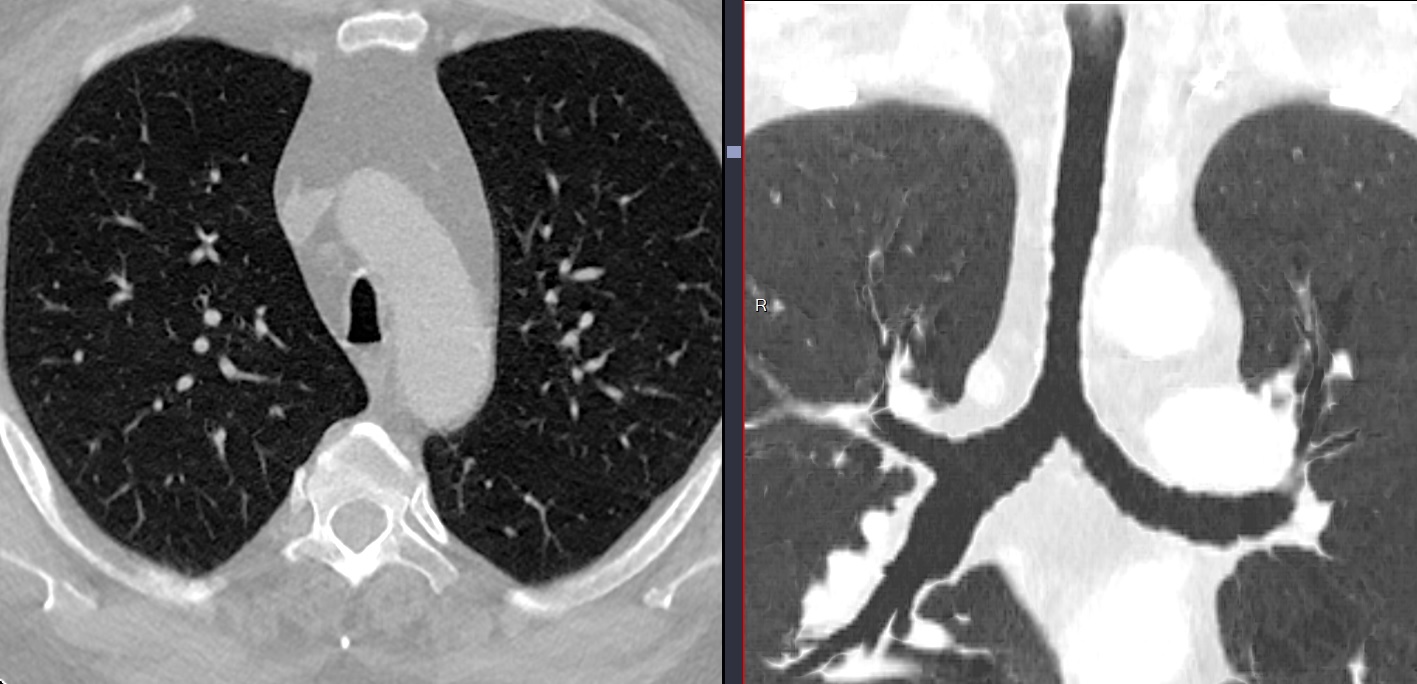

(a) emphysème destructif prédominant (b) Bronchite Obstructive prédominant avec presque pas d’emphysème

Emphysème Destructif Avancé (EDA)

- Expansion de volume des lobules

- Distortions architecturales

- Vasoconstriction vasculaire (l’oligémie se voit bien en MIP)

- Peut prédominer aux bases aussi

Emphysème prédominant Pink Puffer

- Definition théorique >6% de pixels < -950 HU

- Definition théorique <6% de pixels < -950 HU